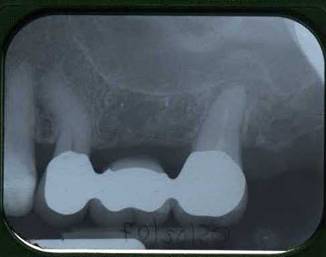

The radiograph shows many characteristics of OAC/OAF; the apexes of tooth 26 were in extremely close approximation to the maxillary sinus, and an area of periapical rarefaction was evident (Fig. 1).

Figure 1

Rx after endodontic therapy of tooth 26.

The radiographic (Fig.2) examination did not underline any discontinuity of the sinus floor, but showed radiographic loss of lamina dura at the inferior border of the maxillary sinus over the involved tooth and the localized swelling and thickening of the sinus mucosa; only close the root of 2.7 a periapical lesion was present; radiopacity of different degrees was evident in sinus space.

Figure 2

Rx after 26 extraction and following rehabilitation with fixed partial prosthesis.